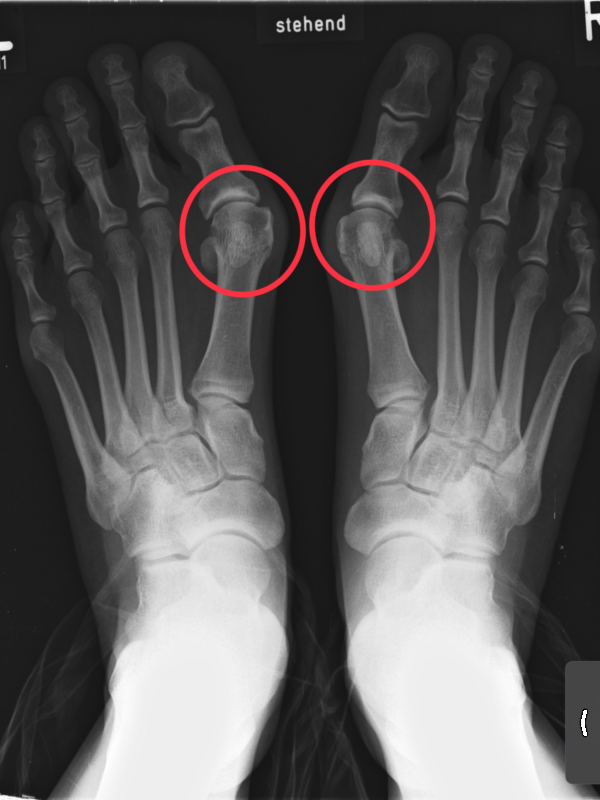

-

- Imatge radiogràfica (R-X) de peu esquerre i dret des d’una visió superior. Es marca en vermell els dos galindons entre la falange 1 i el primer metatarsià de cada peu. Font: Wikipedia.

Són malalties articulars no degudes a infecció o inflamació. Afecten dits, especialment. Un dels exemples és el que col·loquialment es coneix com a galindó o Hallux valgus (deformitat per engruiximent de l’articulació del primer metatarsià amb la primera falange del dit gros del peu). Presenta les següents característiques:

- Etiologia (causes): pot ser de causa genètica i/o per desequilibris musculoesquelètics, tot i que la principal causa és una forma de caminar incorrecta. Es pot presentar en persones amb peu cavus (amb molta curvatura a la planta) o peu valg (que es fica cap endins en caminar), acostuma a associar-se al tipus de calçat (talons alts i prims), estar molt de temps dret. Apareix en la persona adulta i acostuma a ser més freqüent amb l’edat.

- Quadre clínic (simptomatologia): s’associa amb dolor intens, vermellor, inflamació local i limitació del moviment articular.

- Diagnòstic: anamnesi i estudi físic, principalment, observació directa de la zona i estudi biomecànic de la trepitjada. Així mateix, es poden utilitzar proves de diagnòstic per la imatge, com ara radiografia (R-X).

- Tractament: adequació de les sabates, ús de plantilles i/o fèrules correctores i, si el dolor és molt intens, i s’adequa al perfil de la persona, s’opta per cirurgia. La utilització de fàrmacs per alleujar el dolor pot ser indicada, així com tractament local de fred per disminuir la inflamació.